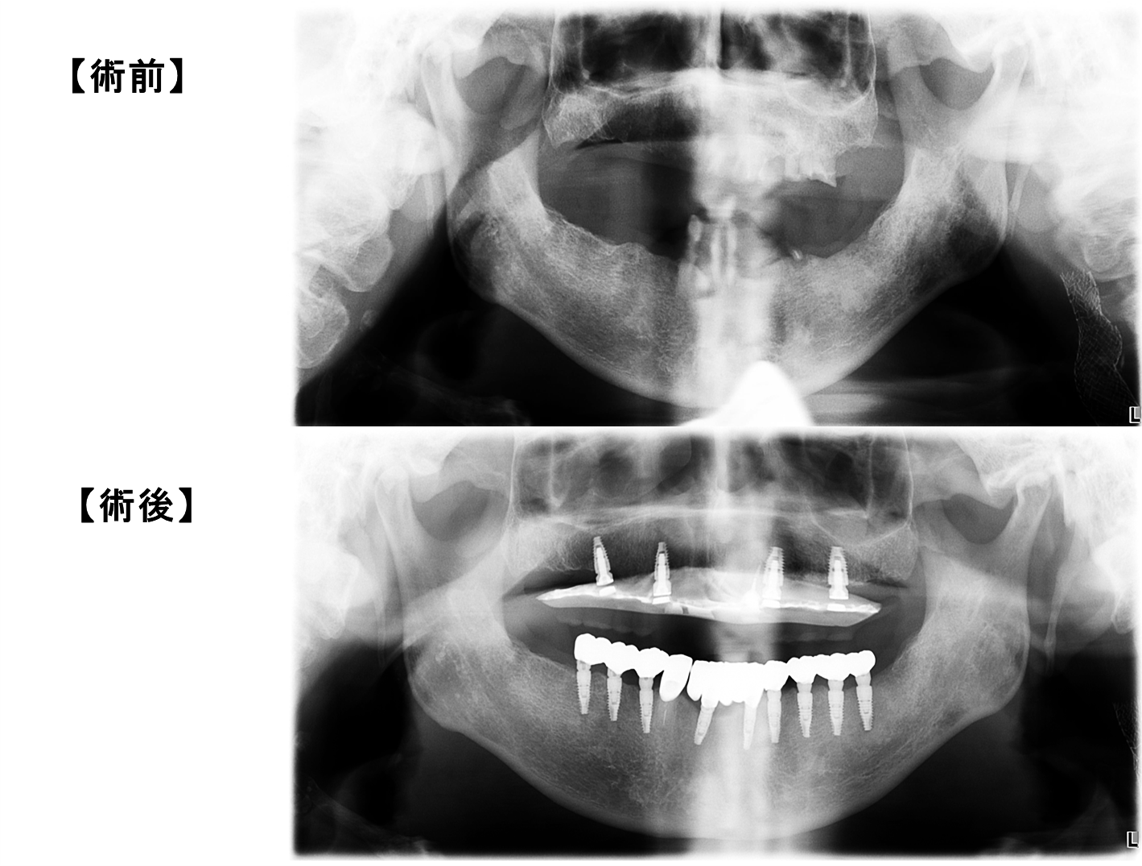

・第2症例は、前回と同様に従来の手術用ガイドでは固定源が難しく、

適用できないとされてきた多数歯欠損の困難なケースです。

コンピュータシュミレーションによって精密に製作されたガイデッドサージェリーでのインプラント手術を行っております。

| 【治療内容】 | 下顎はインプラントフルブリッジ、噛み合せが反対咬合、右側にずれる「かみ癖」のため、上顎はインプラント4本のオーバーデンチャー( 磁性アタッチメント義歯 )下顎は残存歯が1歯の多数歯欠損で手術用ガイドの固定源確保が困難でありましたが、インプラントをCTスキャンデータで作製した手術用ガイドを用いて9本埋入し、固定式3本連結のブリッジを3装置としました。

| 【治療期間・回数】 | 通院20回 、11ヵ月

| 【費用】 | 術前CT・診断29,700円/ガイデッドサージェリー91,300円/1次手術154,000円×13本、2次手術52,800円×13本/ブリッジ装着:前歯121,000円×6本,臼歯77,000円×6本/磁性アタッチメント55,000円×4・チタン床義歯264,000円、標準総額 380万円(税込)

| 【リスク・副作用】 | 手術後に炎症・痛み・腫れが生じる場合がありますが、下顎インプラントに関しましては、術前CTで血管・神経走向を確認して治療を進めるので、麻痺など症状が起こることはありません。